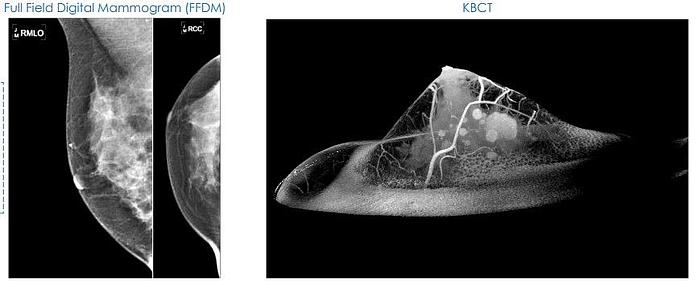

The Koning Breast CT (KBCT) offers a pioneering approach to breast imaging by providing true 3D, isotropic imaging without the need for breast compression, enhancing patient comfort with prone positioning. Its rapid scan time of 7 seconds enables high throughput while maintaining superior detection capabilities, identifying smaller and earlier cancers effectively. The system is designed to match the radiation dose of traditional mammography, minimizing patient exposure. This advanced imaging technology promotes greater clinical insights while reducing recalls, thereby optimizing workflow efficiency for healthcare providers. With minimal training required, the KBCT supports improved economic outcomes by integrating capital equipment efficiency, potentially replacing multiple devices within a compact footprint. This leads to reduced facility modification costs and contributes to more sustainable healthcare practices. The benefits extend to patients as they experience greater compliance due to the non-invasive procedure and reduced discomfort. From an economic standpoint, the system assists in lowering costs per case, the overall cost of breast cancer management, and extraneous costs associated with false positives, making it a compelling choice for modern healthcare facilities seeking to enhance their breast imaging services.

Koning True 3D Breast CT (KBCT) provides significant clinical and economic benefits to all parties in health care ecosystem!

- True 3D isotropic imaging